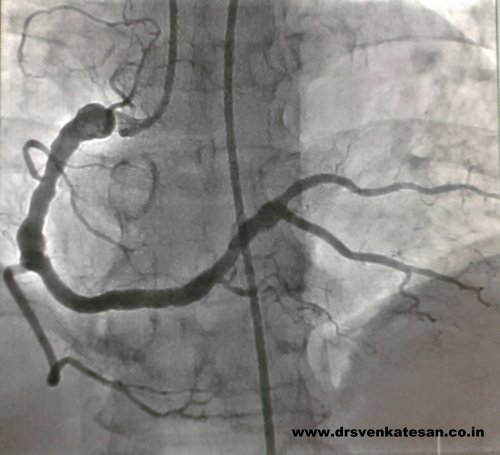

Here is a different facet of atherosclerosis , A middle aged man surprised us with this coronary angiogram . Instead of obstructing the flow the coronary vessel begins to dilate. This is due to a medial weakness .(The media for some reason begins to give way rather than proliferate to the atherogenic stimuli.)

One may wonder why he underwent CAG when obstruction is least expected in such a vessel ! It was paradox of sorts , this man in spite of his wide bore coronary artery , was prone for coronary thrombus and one such episode landed him in our CCU . ( Please note both faces of atherosclerosis “obstructive and dilatory” can manifest in the same vessel in different combination.)

This angiogram may be reported as any one of the following

- Diffuse atherosclerosis

- Diffuse atherosclerosis with focal dilatation and aneurysm formation

- Coronary ectasia